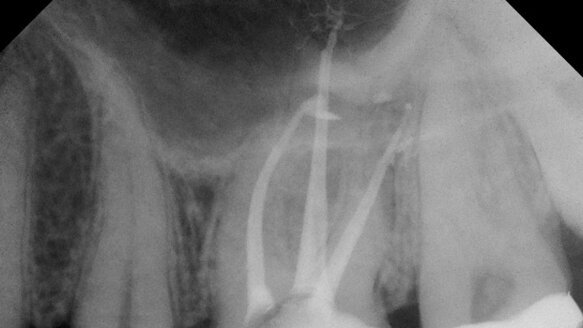

Where should I fit my master cones and warm carrier-based devices to?

If cone fit is correct, the master cone should terminate at the MC and only possess intimate tugback in the apical 3-4 mm. The cones should resist coronal displacement while seated at the MC.

Warm carrier-based obturation devices such as the RealSeal One Bonded Obturator should also be placed to the MC. If cone fit and carrier fit are correct, and if irrigation is adequate, the degree of extrusion of sealer and obturation material is clinically irrelevant. In essence, the clinician does not need to back away from the MC.

Coincident though to that recommendation, it is vital for the clinician to be especially careful throughout the treatment process to work up to the MC, never violate the MC with rotary nickel titanium files and have ideal cone fit. Placing sealer with the Skini syringe and Navi tips (Ultradent, South Jordan, Utah) provides tremendous precision in sealer placement and avoids unnecessary extrusion.